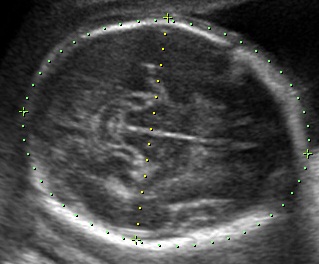

ultrasonda bebeğin karın çevresinin büyük olması

ultrasonda bebeğin karın çevresinin büyük olması.